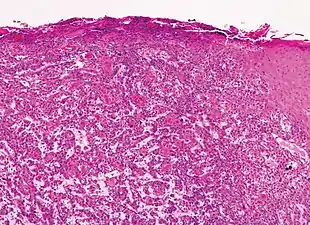

Histopathologically, the epidermis in SCC in situ (Bowen’s disease) will show hyperkeratosis and parakeratosis. There will also be marked acanthosis with elongation and thickening of the rete ridges. These changes will overly keratinocytic cells which are often highly atypical and may in fact have a more unusual appearance than invasive SCC. The atypia spans the full thickness of the epidermis, with the keratinocytes demonstrating intense mitotic activity, pleomorphism, and greatly enlarged nuclei. They will also show a loss of maturity and polarity, giving the epidermis a disordered or “windblown” appearance.

Two types of multinucleated cells may be seen: the first will present as a multinucleated giant cell, and the second will appear as a dyskeratotic cell engulfed in the cytoplasm of a keratinocyte. Occasionally, cells of the upper epidermis will undergo vacuolization, demonstrating an abundant and strongly eosinophilic cytoplasm. There may be a mild to moderate lymphohistiocytic infiltrate detected in the upper dermis.[12]

Histopathology of squamous cell carcinoma in situ (black arrow), compared to normal skin, showing marked atypia.

Squamous cell carcinoma in situ, showing prominent dyskeratosis and aberrant mitoses at all levels of the epidermis, along with marked parakeratosis.[12]